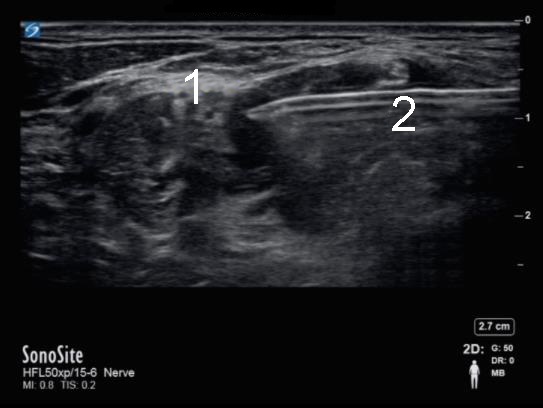

Image - Bloc interscalénique gauche - Pendant l'injection

Plexus brachial

Aiguille